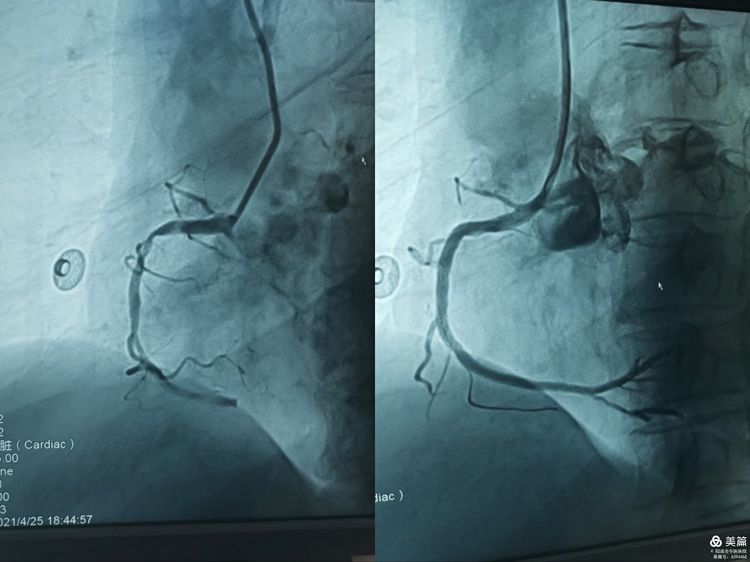

近日,一位66岁女性因突发胸闷到我院心血管病科就诊,经诊断为急性心肌梗死,科室主任王明辉带领团队认真讨论后,决定为患者行急诊经皮冠状动脉介入治疗(PCI)。

随着急诊PCI流程的启动,导管室医务人员迅速到位,经心血管病科介入团队成员经过紧张有序、争分夺秒的手术操作,顺利开通了患者闭塞的冠状动脉血管并植入一枚支架,患者胸痛症状迅速缓解,病情转危为安。

当天晚上8时许,“铃铃铃……”心血管病科值班电话响起,“急诊科收治一名59岁的突发胸痛的患者,请你们科室会诊”。经心血管病科值班医师张永梅会诊后诊断为急性心肌梗死,刚下班到家的王明辉主任立即返回医院查看患者并决定立即进行急诊PCI。心血管病科冠脉介入团队再一次启动导管室为患者打通了血管,开启了患者的生命之门。

急性心肌梗死的患者往往病情危重、变化快,急诊PCI术是治疗急性心肌梗死最重要的方法之一,治疗越早、效果越好。短短的6个小时之内,心血管病科以最快的速度实施了两台急诊PCI术,挽救了他们急性心肌梗死患者垂危的生命。实施急诊PCI风险高、技术难度大,不仅考量术者的技术和处理病人的综合能力,更要求有一支经验丰富、训练有素、团结合作的心血管内科介入团队。心血管病科将继续秉承“时间就是生命,时间就是心肌”的救治理念,不断加强学科建设,提高诊疗能力,为建设胸痛中心打下坚实的基础。 (通讯员/心血管病科 李羚荧)